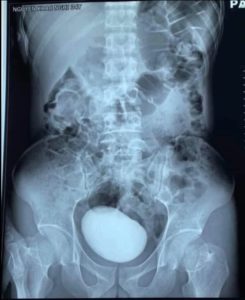

Tras un breve examen en el que los especialistas pudieron notar cómo su abdomen estaba más duro y tenso de lo normal, decidieron hacerle una tomografía (CT) para obtener una imagen más precisa de lo que había en su interior. Lo que no se esperaban, sin embargo, era encontrarse con una enorme masa redonda alojada en su abdomen.

Durante la operación, los cirujanos extrajeron un cálculo de más de diez centímetros de largo, cuyo peso superaba los 400 gramos.